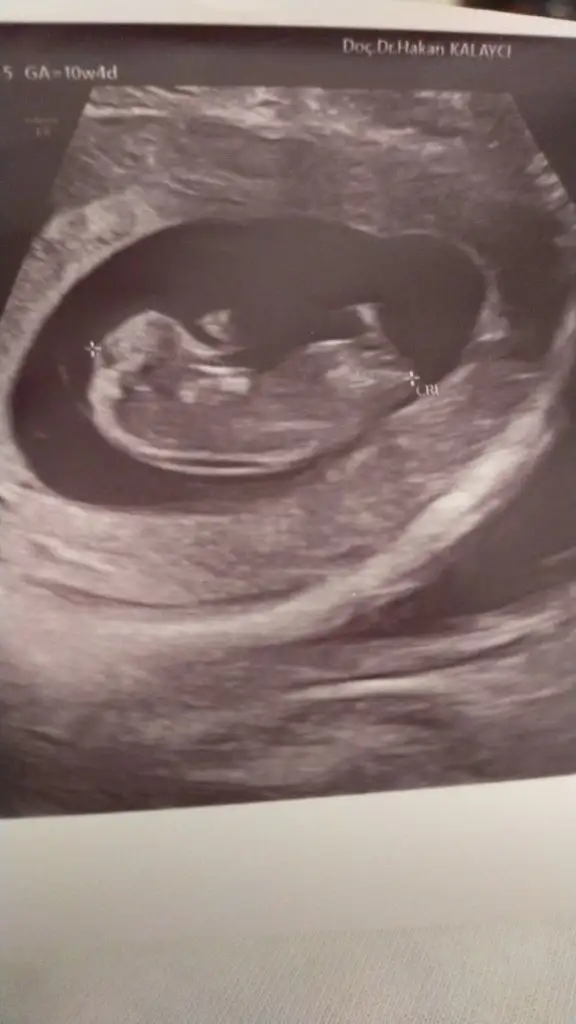

Nub olarak mı baktın yavrum valla bende bilemedim cihazda daha netti de kağıtta niye böyle çıktı 😅😅

Evet kuzum nub olarak baktım💕🌸 aynen kızım olacak ismini bile koyduk İpek🌱

Eklentiler

• IMG-20220307-WA0003.webp

IMG-20220307-WA0003.webp

32 KB · Görüntüleme: 59

Valla ben kıza benzettim bakalım sende de tutturabilecek miyim:) net fotoğraflarda daha cok garanti verebiliyorum ama senınkı gerçekten biraz yorum isteyen bir açıda bakalım göreceğiz😁